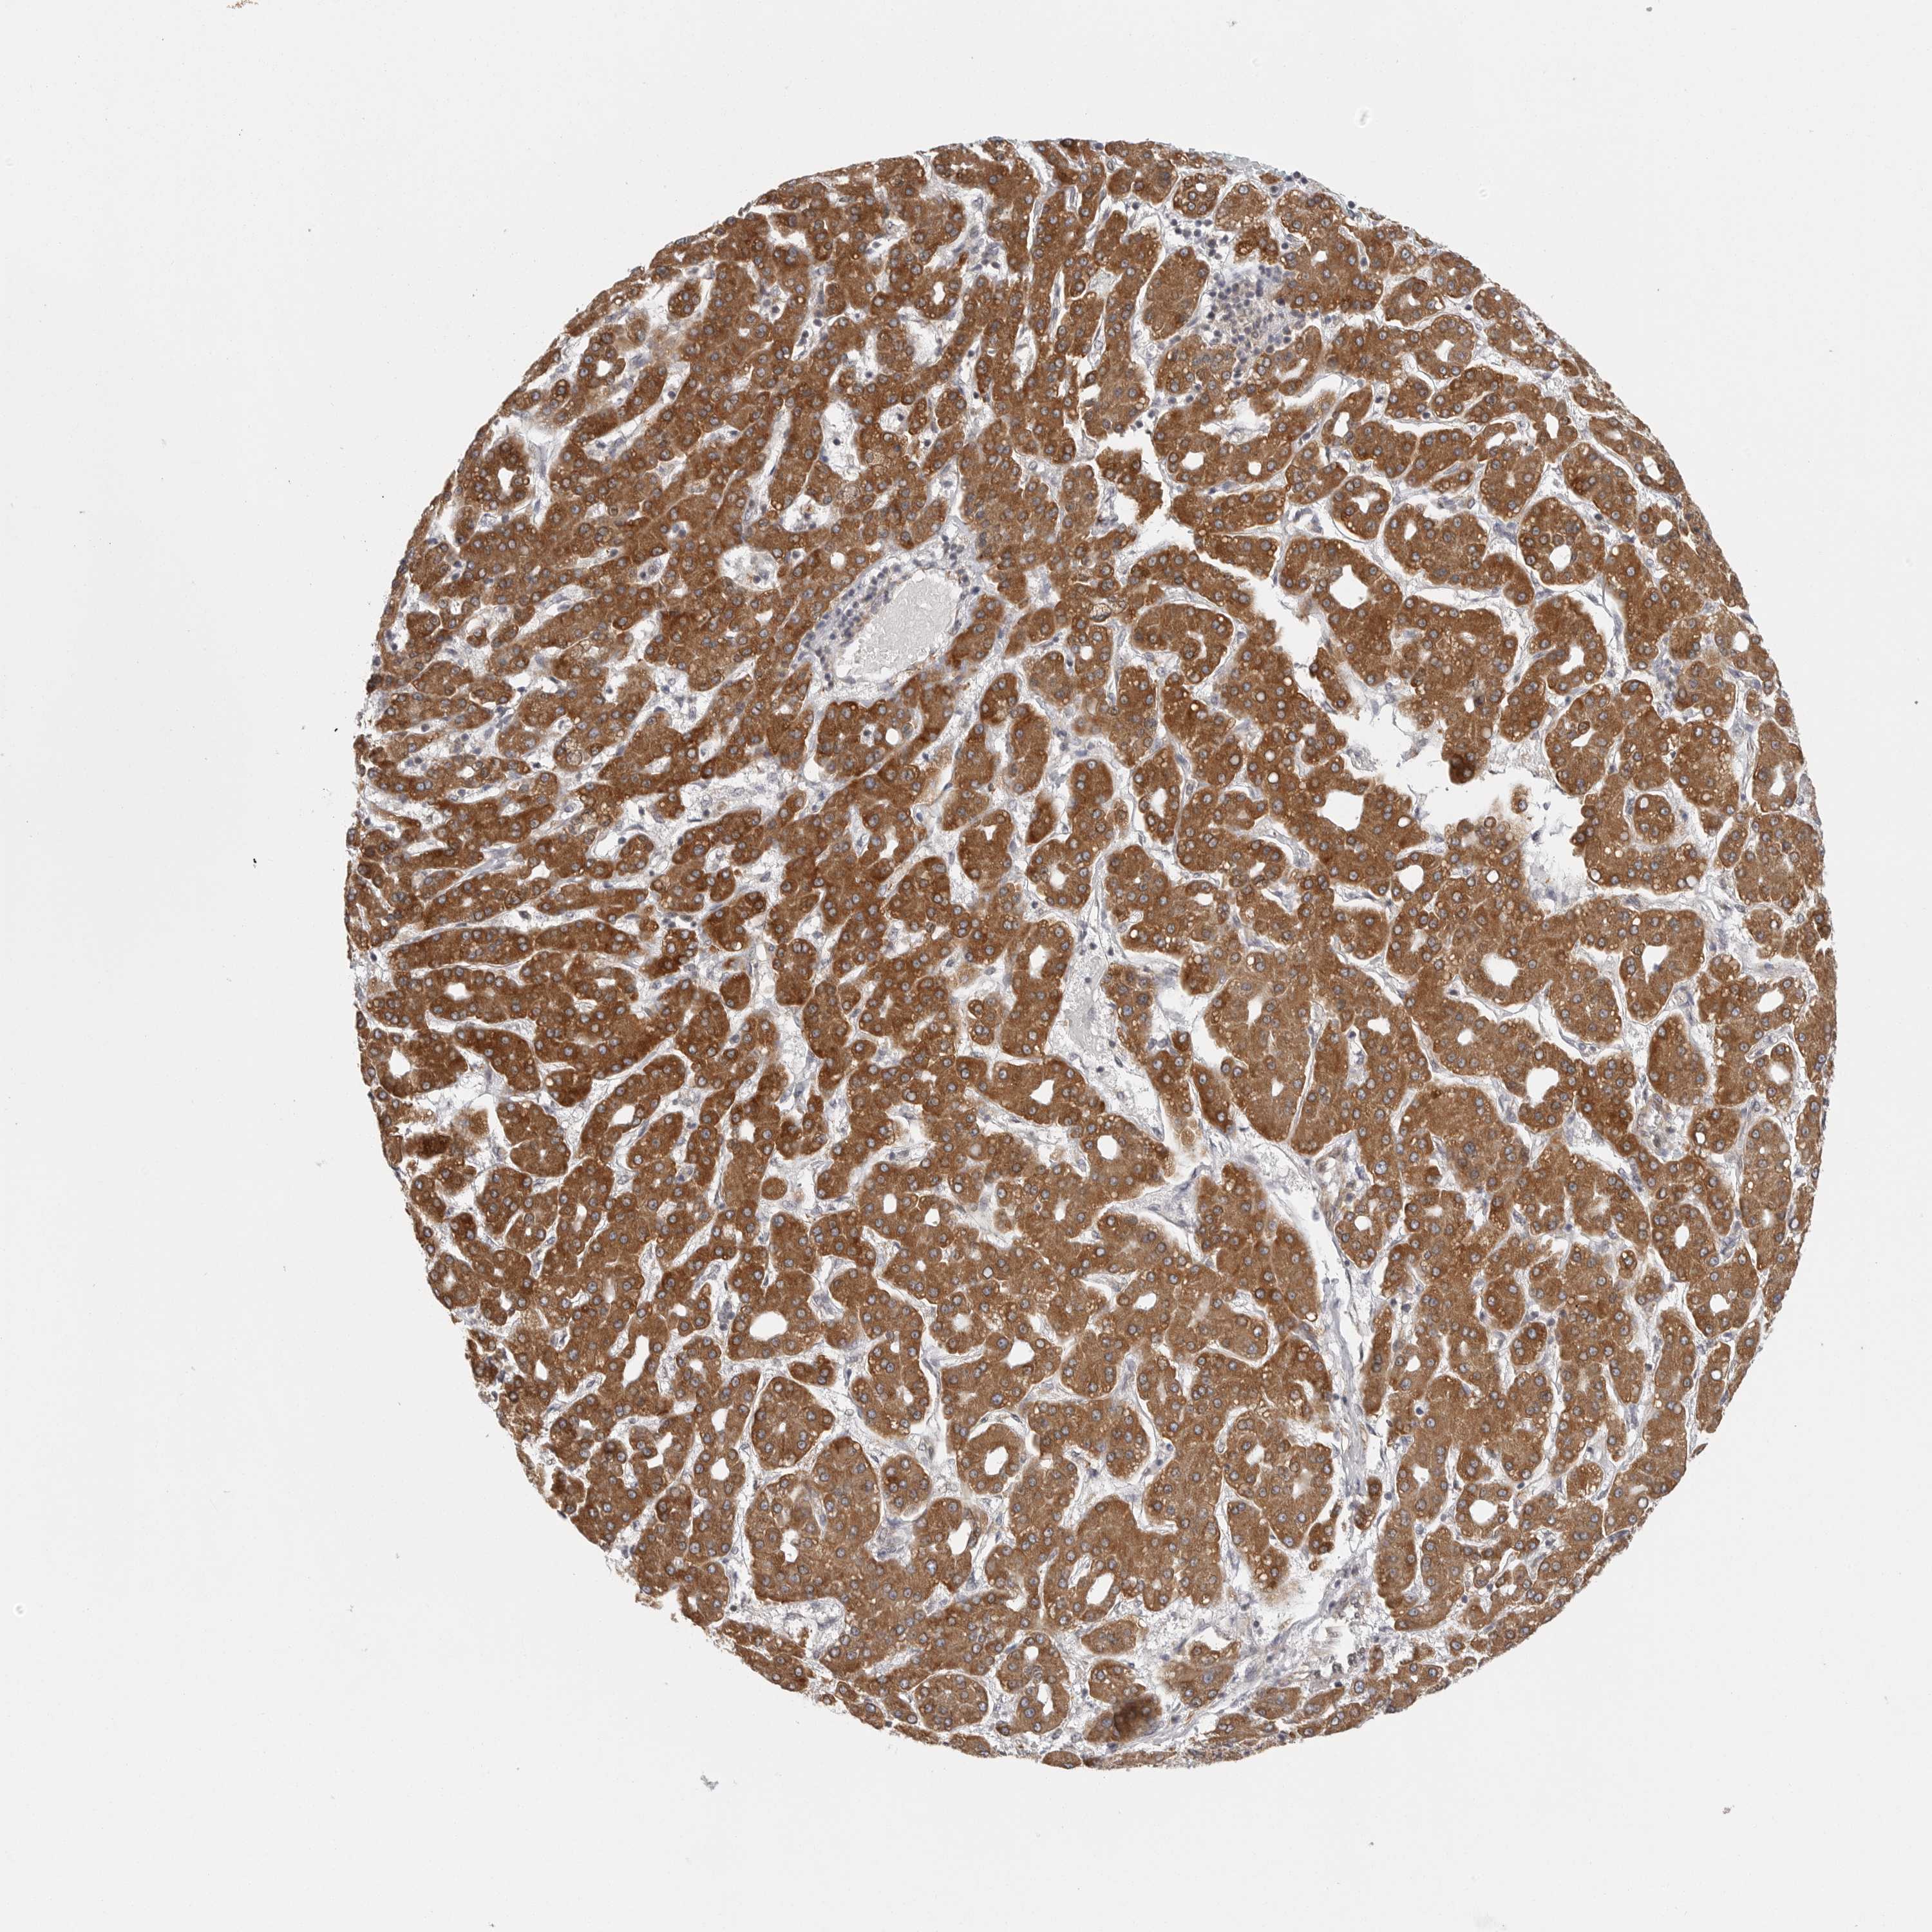

LIVER CANCER - Protein expressioni

A mouse-over function shows sample information and annotation data. Click on an image to view it in a full screen mode. Samples can be filtered based on level of antibody staining by selecting one or several of the following categories: high, medium, low and not detected. The assay and annotation is described here.

Note that samples used for immunohistochemistry by the Human Protein Atlas do not correspond to samples in the TCGA dataset.

Antibody stainingi

Antibody staining in the annotated cell types in the current human tissue is reported as not detected, low, medium, or high, based on conventional immunohistochemistry profiling in selected tissues. This score is based on the combination of the staining intensity and fraction of stained cells.

Each image is clickable and will lead to virtual microscopy that enables deeper exploration of all samples and also displays staining intensity scores, fraction scores and subcellular localization as well as patient and tissue information for each sample.

Antibody HPA027262

Antibody HPA078737